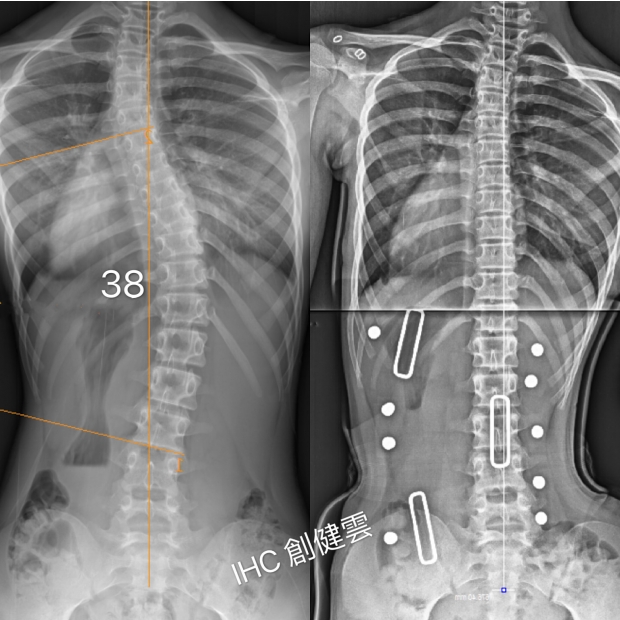

15歲脊椎側彎女孩

胸腰彎38度